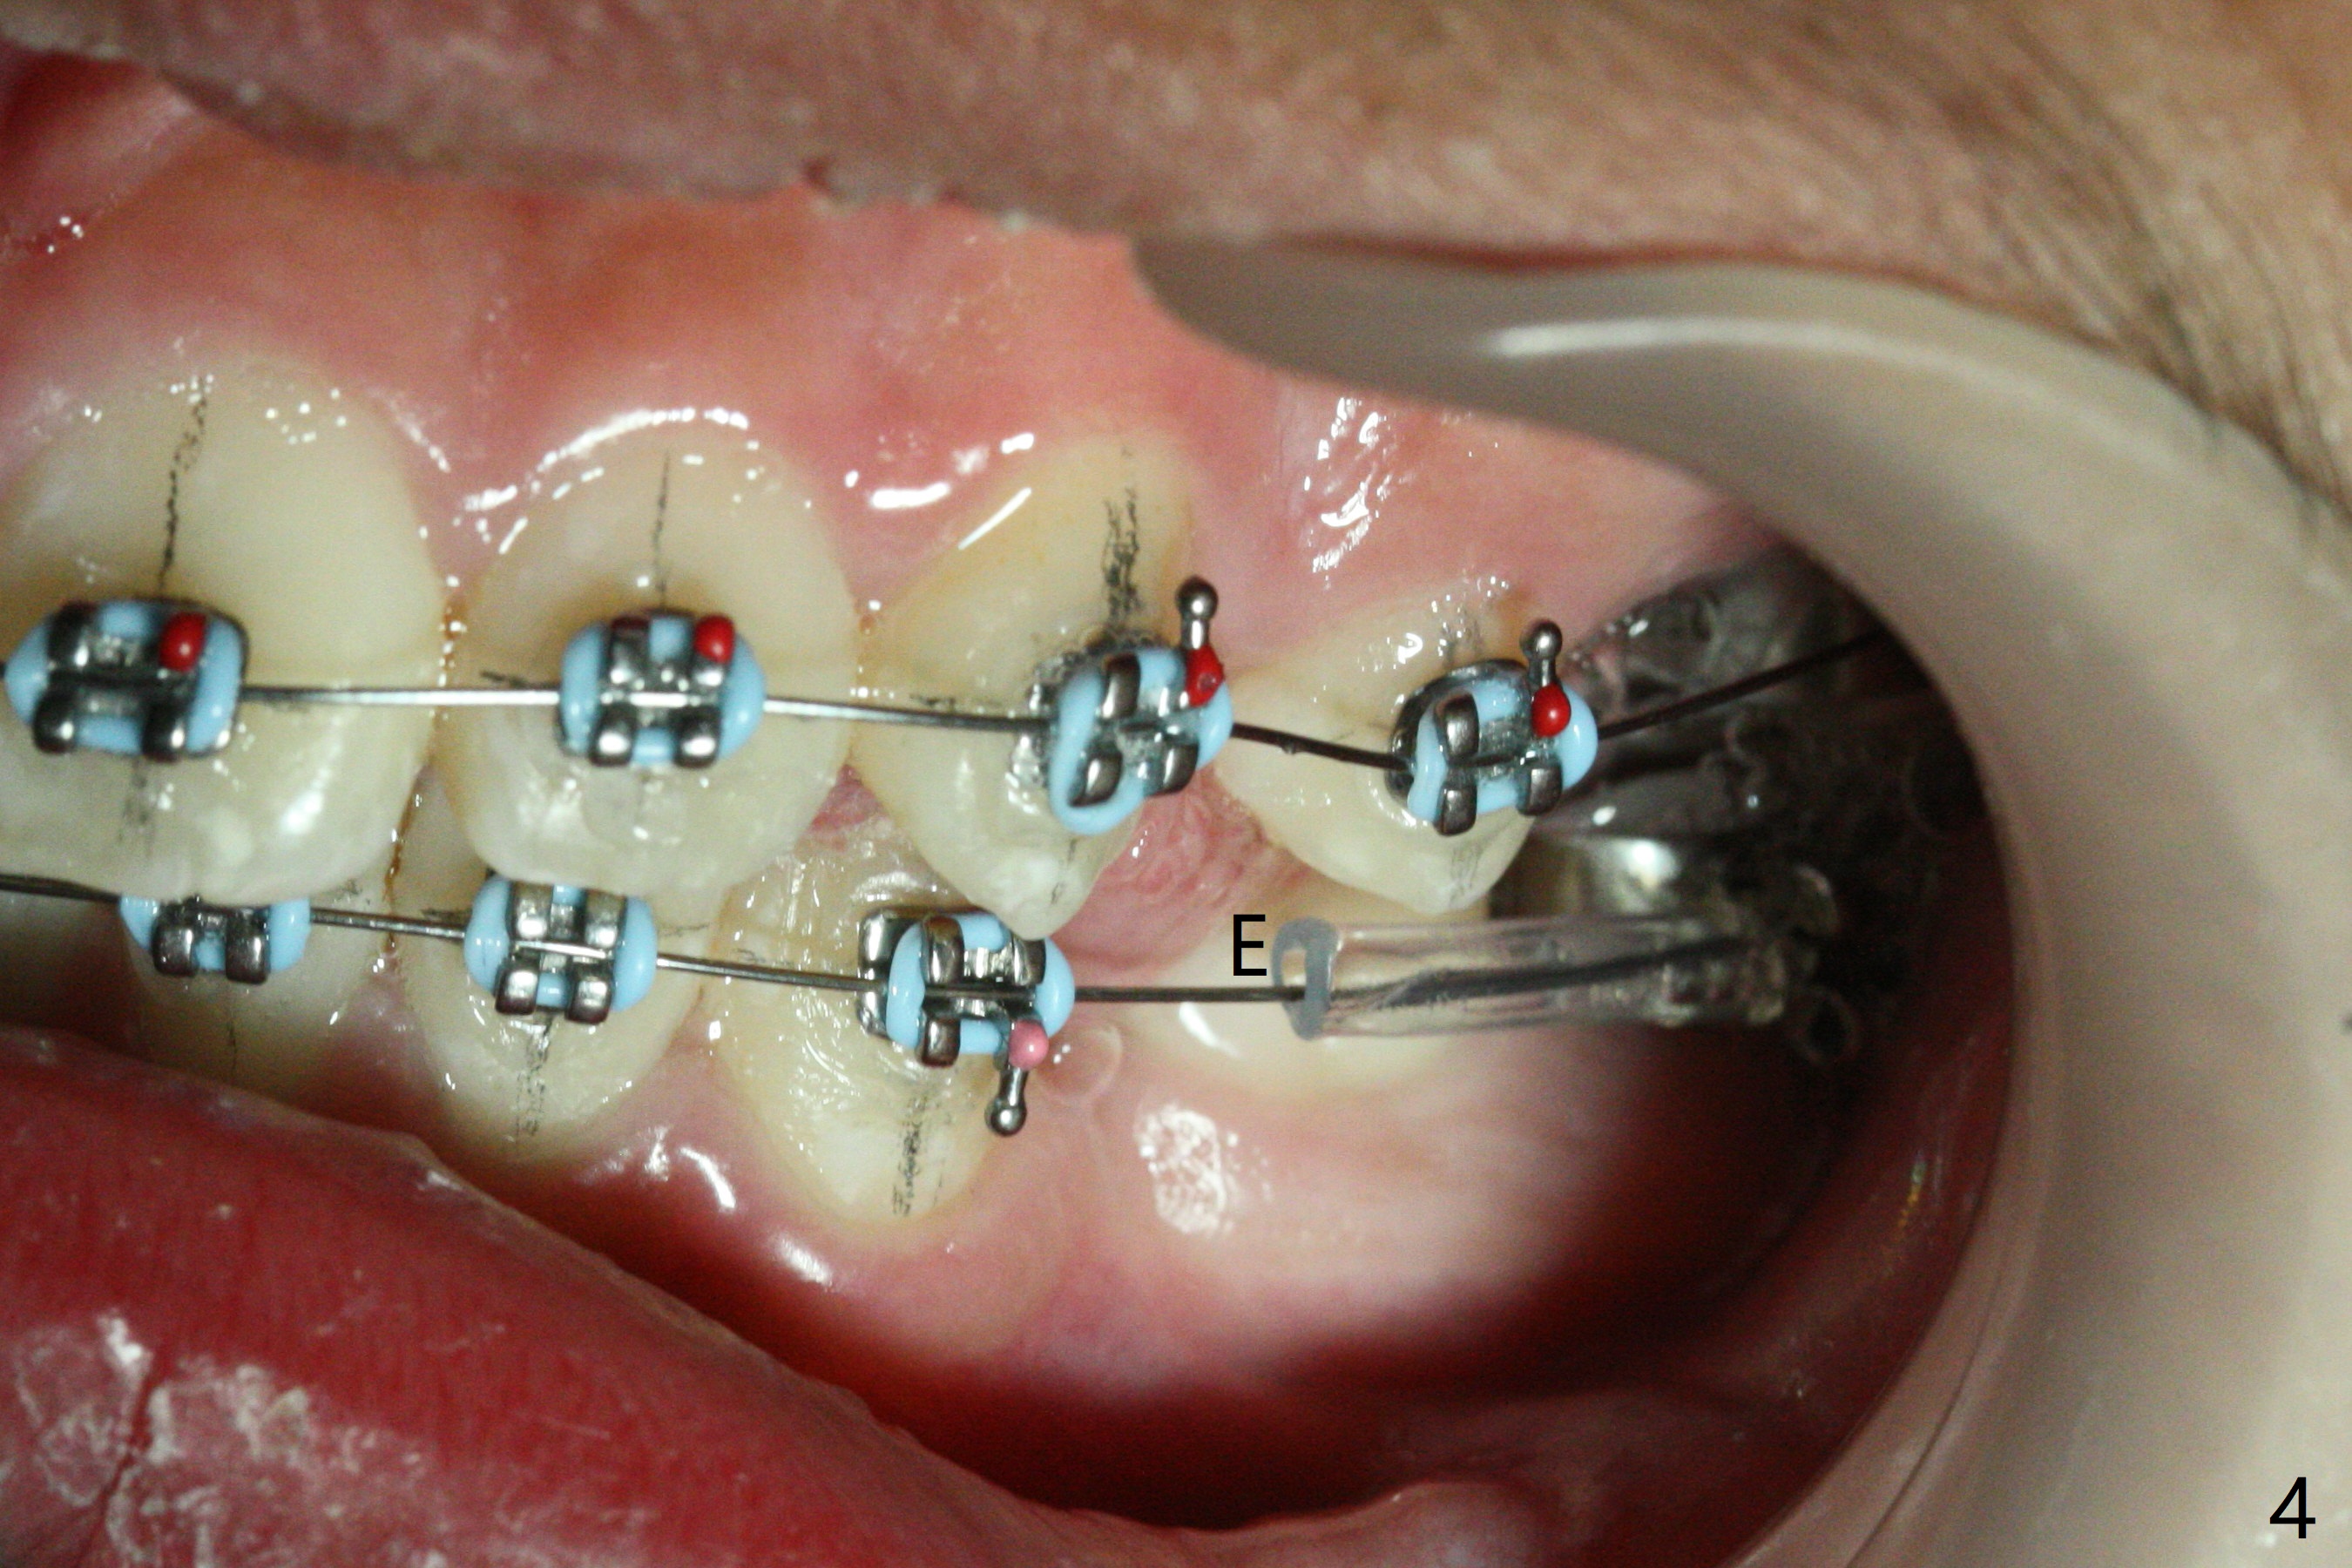

Pre-operative cephalometric X-ray shows convex facial profile (Fig.1). In fact tracing (a few days after banding) shows bimaxillary protrusion (SNA, SNB (88 and 87 degrees vs. 82, 80 (normal)). It appears that extraction orthodontics is indicated (UR4, UL5 (impacted) and LEs). The facial and upper dental midlines seem to coincide (Fig.2). No brackets or bands are placed at UR4 (because of non-cooperative (hyperactive)), LEs (Fig.3,4), or L7s (incomplete eruption, data not shown). Note wire bending between the canines and incisors, as related to correction of overbite. Shrinkable tubes are used in the region without bracket to prevent tissue injury. The upper arch seems to elongate (Fig.5, as compared to the lower one (Fig.6)). It appears that UR4 and UL5 should be extracted for normal profile and alignment. Cephalometric tracing shows that SNA and SNB are 79 and 85º, respectively, suggesting extraction (Fig.7).